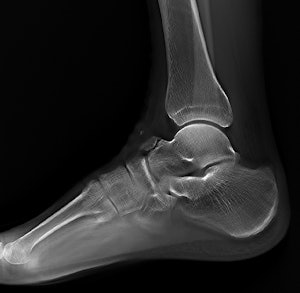

Clinical image of an x-ray examination of the ankle joint. Copyright: Radiology Department, University Hospital Erlangen, Germany. Image courtesy of Siemens.The machine can record static, dynamic, and real-time 3D sequences, and the full range of its potential applications is still to be explored. But there are clinical applications in which it already appears to have advantages over CT, notably in investigations of upper limb fractures in obese patients and weight-bearing lower-limb bone examinations of diabetics, he added.

Tomosynthesis image of an ankle taken with Shimadzu's RADspeed Pro digital radiography system.The emphasis of Philips' researchers has been on developing technologies for improving diagnostic quality while eliminating inefficiencies when using mobile digital radiography systems at the patient's bedside. The new SkyFlow scatter correction algorithm reduces the effect of scattered radiation for nongrid bedside chest exams, allowing the operator to obtain DR images with grid-like contrast, but avoiding the time and effort involved in attaching and detaching a grid.